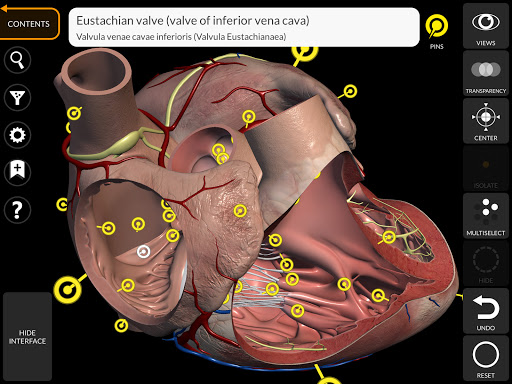

"Anatomía - Atlas 3D" permite estudiar la anatomía humana de forma fácil e interactiva.

A través de una interfaz sencilla e intuitiva es posible observar cada estructura anatómica desde cualquier ángulo.

Los modelos anatómicos 3D son especialmente detallados y con texturas de hasta una resolución de 4k.

La subdivisión por regiones y las vistas predefinidas facilitan la observación y el estudio de partes individuales o grupos de sistemas y las relaciones entre los diferentes órganos.

MODELOS ANATÓMICOS 3D

nervioso • Sistema respiratorio • Sistema digestivo • Sistema urogenital (masculino y femenino) • Sistema endocrino • Sistema linfático • Sistema ocular y auditivo CARACTERÍSTICAS • Interfaz sencilla e intuitiva • Rotar y hacer zoom en cada modelo en el espacio 3D • Opción para ocultar o aislar uno o varios modelos seleccionados • Filtro para ocultar o mostrar cada sistema • Función de búsqueda para encontrar fácilmente cada parte anatómica • Función de marcador para guardar vistas personalizadas • Rotación inteligente que mueve el centro de rotación automáticamente • Función de transparencia • Visualización de músculos a través de niveles de capas desde las superficiales hasta las más profundas • Al seleccionar un modelo o un pin, aparece el término anatómico relacionado • Descripción de los músculos: origen, inserción, inervación y acción • Mostrar/ocultar interfaz de usuario (muy útil con pantallas pequeñas) MULTILINGÜE • Los términos anatómicos y la interfaz de usuario están disponibles en 11 idiomas: latín, inglés, francés, alemán, italiano, portugués, turco, ruso, español, Chino, japonés y coreano • Los términos anatómicos se pueden mostrar en dos idiomas simultáneamente REQUISITOS DEL SISTEMA • Android 8.0 o posterior, dispositivos con al menos 3 GB de RAM Reversi